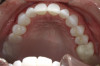

A 52-year-old female patient with history of lost retainers that she had used for a previous orthodontic treatment presented with minor orthodontic relapse during a hygiene visit. Her chief concern was that her lateral incisors were "starting to flare forward," as she had not been compliant with her retainers, and she expressed a desire for an affordable clear aligner solution. Clinically she presented with upper and lower anterior tooth crowding of less than 3 mm, specifically lower anterior teeth Nos. 23, 24, and 25, with a reverse curve of Spee of less than 2 mm on the lower anterior teeth (Figure 1 through Figure 3). The upper anterior arch presented with lateral incisor buccal rotations of less than 15 degrees on teeth Nos. 7 and 10 from an overjet view (Figure 4). The patient's oral hygiene was within normal limits, with stage one gingivitis, based on the new multidimensional staging and grading system of the American Academy of Periodontology and the European Federation of Periodontology that was adopted in 2017.12 The patient also presented with class I bite classification with gingival abfraction on both the anterior and posterior arches, with visibly missing class V restorations (Figure 5 and Figure 6).

At the same office visit, the patient's records with photographs, digital scans (Figure 7 and Figure 8), and periodontal health evaluation were uploaded and submitted through the clear aligner partner company's portal for evaluation by the treating dentists and orthodontists. Subsequently, the patient continued to receive clear aligner treatment with periodic aligner check-in visits via teledentistry from the treating clinician and team member, using the network practice only for hygiene and in-office routine dental examinations.

Fig 2. Patient presented with upper and lower anterior tooth crowding

of less than 3 mm. Figure 1: Anterior view. Figure 2: Upper arch. Figure 3: Lower

arch.

Figure 2

Fig 3. Patient presented with upper and lower anterior tooth crowding

Figure 3

Fig 7. Digital scan of upper anterior

teeth.

Figure 7

Fig 8. Digital scan of lower arch.

Figure 8